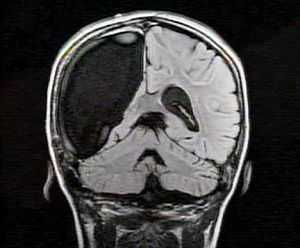

• МРТ головного мозга;

МРТ головного мозга по эпилептологической программе с внутривенным контрастным усилением (проводится на томографах высокого разрешения с магнитом не менее 1.5 Тл, аппараты с магнитом 3 Тл предпочтительнее), включающее следующие программы: Sag T1 Flair, Ax T2 Flair, Ax T2 Propeller, Ax FSPGR 3D, Ax DWI b1000, +C-Ax FSPGR 3D, Cor T2 HIGH Resolution, Apparent Diffusion Coefficient, Ax SWAN;